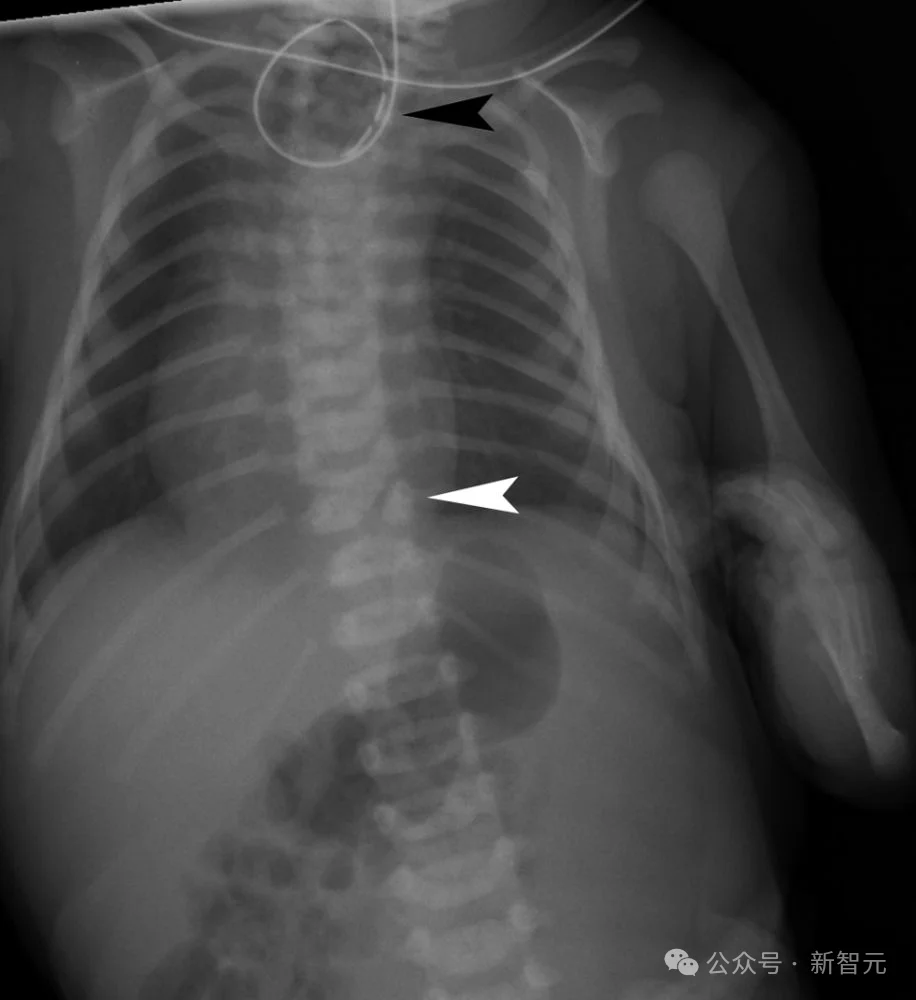

这是一个刚满月的宝宝,摆在医生面前的就这三样东西:一张胸部X光片、一张足部外观照、还有一张血常规化验单。

症状很明显但很分散,就像几个不相干的毛病,这就很考验模型捕捉碎片信息和综合分析的能力。

但WiseDiag V2并没有盲人摸象,而是整体思考:

在胸部X光片,锁定了食管闭锁和半椎体发育异常;

在足部外观照中精准识别了足部的马蹄内翻;

通过化验单的数值和胸部X光片读出了吸入性肺炎的风险。

综合所有信息给出正确的诊断结果——VACTERL联合征。

VACTERL联合征是一种罕见的非随机先天性多系统发育畸形组合,通常由至少三种特定器官缺陷组成:脊柱畸形(V)、肛门闭锁(A)、心脏缺陷(C)、气管食管瘘/食管闭锁(TE)、肾脏畸形(R)和肢体异常(L)